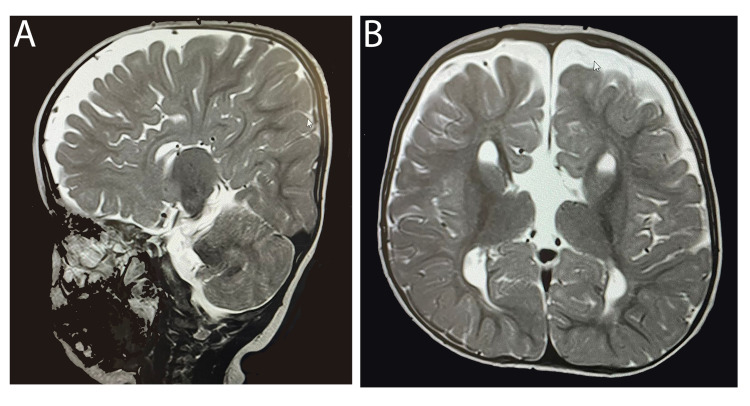

一名 14 個月大的女童,有全身發(fā)育遲緩、畸形特征(眼距過遠(yuǎn)、眼球突出、上瞼下垂、小頜畸形)和弱視病史,被轉(zhuǎn)診至佳學(xué)基因遺傳病罕見病基因檢測案例協(xié)作單位。就診原因是言語和語言發(fā)育遲緩。 她的父母是一級近親,被診斷患有雙側(cè)重度至極度SNHL,并在 9 個月大時安裝了雙側(cè)助聽器。 然而,在隨訪中沒有發(fā)現(xiàn)使用助聽器有明顯的好處。 磁共振成像 (MRI) 顯示胼胝體有效發(fā)育不全(圖 1)。 此外,全外顯子組測序顯示 LRP2 基因突變,證實(shí)了 DBS 的診斷。 在 18 個月大時,她的智商測試成績?yōu)?75 分。

An external file that holds a picture, illustration, etc.

Object name is cureus-0014-00000021063-i01.jpg

病例 1 的 MRI:(A) 矢狀切面 (B) 冠狀切面顯示胼胝體有效發(fā)育不全